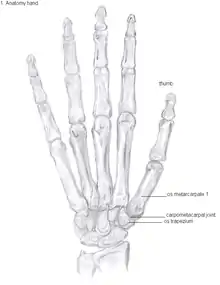

Anatomy

The TMC joint is a synovial joint between the trapezium bone of the wrist and the metacarpal bone at the base of the thumb. This joint is a so-called saddle joint (articulatio sellaris), unlike the CMC joints of the other four fingers which are ellipsoid joints.[17] This means that the surfaces of the TMC joint are both concave and convex.

The TMC joint is stabilized by 16 ligaments.[19] Of these ligaments, the deep anterior oblique ligament, also known as the palmar beak ligament, is considered to be the most important stabilizing ligament.[20]